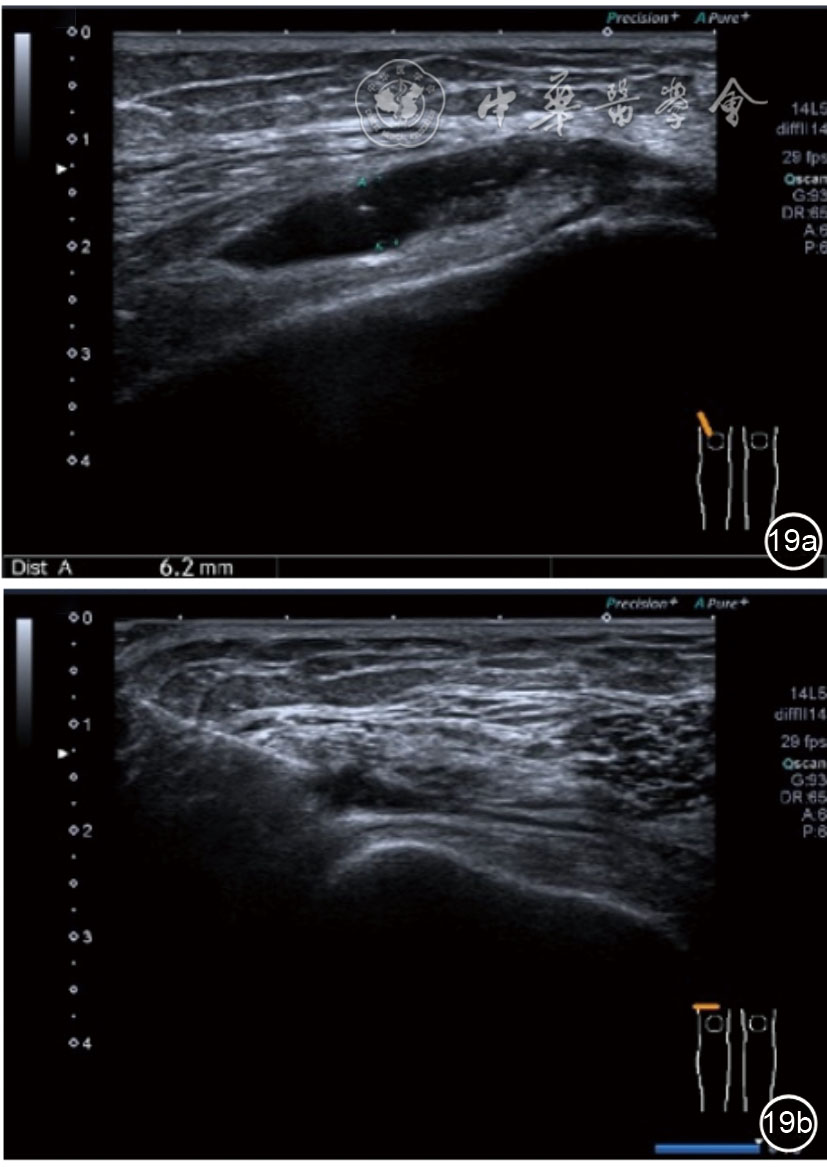

髂胫束的最佳显示切面为长轴切面,采用高频探头,扫查深度<3 cm。超声表现胫骨附着点处骨皮质不规则,髂胫束增厚,回声减低,其周围组织水肿,血流增加(图26)。股骨髁部肿胀、增厚,回声减低,超声触诊可能诱发股骨外侧髁处的疼痛。部分患者可见髂胫束滑囊扩张,内为无回声积液(图27)。

图26 超声图像显示胫骨附着点处骨皮质不规则,髂胫束增厚,回声减低,其周围组织水肿,血流增加

图27 超声图像显示股骨髁部肿胀、增厚,回声减低,部分患者可见髂胫束滑囊扩张